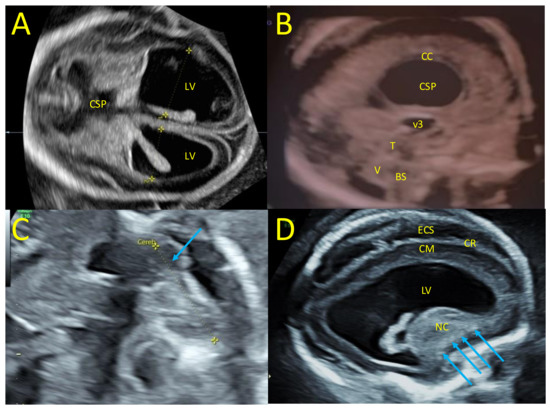

3. Case Report